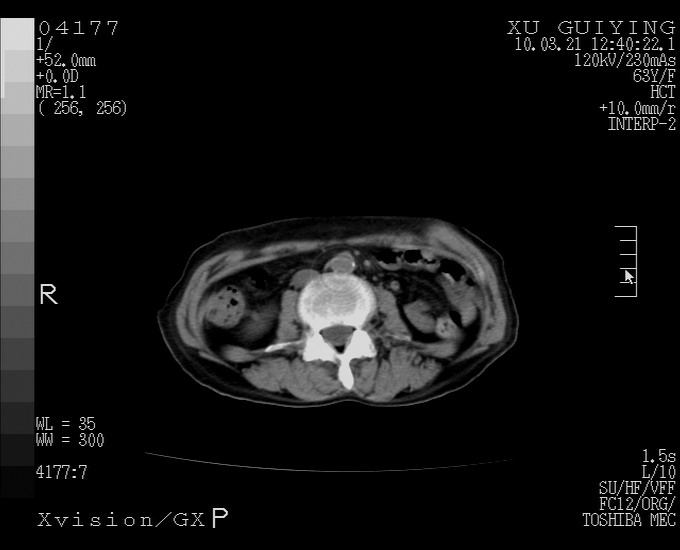

标题: CT25230:女,63岁,萎缩性胃炎病史,患者明显黄染,不能进 [打印本页]

标题: CT25230:女,63岁,萎缩性胃炎病史,患者明显黄染,不能进

怎么没有增强呢?胆囊那么大,密度有些高啊。

慢性胆囊炎,胆囊占位不排除,建议增强或彩超。

考虑胆囊炎 不除外泥沙样结石

胆囊体积增大,胃窦壁增厚

胆囊体积增大,密度不均匀,结石不除外;胃壁增厚,考虑胃癌,建议增强。

胆囊体积增大,密度增高,较均匀,外缘也较光滑,应考虑胆囊炎。因为胃未充盈,不好说壁增厚。肝左叶及脾门处见低密度灶,有可能是血管瘤,不排除囊肿。建议超声检查或强化。

这就是江湖人称的“内科黄疸”, 肝内胆汁淤积症(ic)?